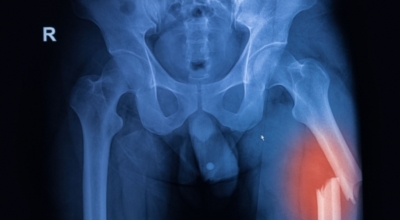

나이가 들면 흔히 생기는 질환 중 하나입니다. 관절을 보호하고 있는 연골의 손상이나 퇴행성 변화로 인해 관절을 이루는 뼈와 인대 등에 손상이 생겨 염증과 통증이 발생하는 질환입니다. 고관절 쪽 연골이 닳게 되면서 망가지게 되고 또 쉽게 없어지지 않는 통증에 시달릴 수 있습니다.